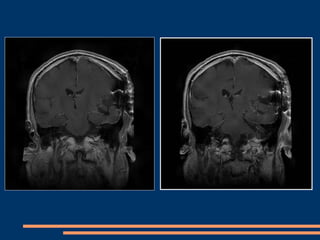

IRM post-opératoire à J 15

IRM post-opératoire à 3 mois

IRM post-opératoire  3 mois